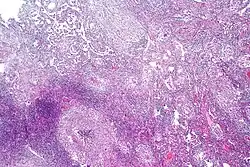

Chest X-ray and CT

Tuberculosis creates cavities visible in x-rays like this one in the patient's right upper lobe.

CT scan of peritoneal tuberculosis, a form of extrapulmonary tuberculosis. The omentum and peritoneal surfaces are thickened (arrows).[14]

In active pulmonary TB, infiltrates or consolidations and/or cavities are often seen in the upper lungs with or without mediastinal or hilar lymphadenopathy or pleural effusions ( tuberculous pleurisy). However, lesions may appear anywhere in the lungs. In disseminated TB a pattern of many tiny nodules throughout the lung fields is common - the so-called miliary TB. In HIV and other immunosuppressed persons, any abnormality may indicate TB or the chest X-ray may even appear entirely normal.

Abnormalities on chest radiographs may be suggestive of, but are not necessarily diagnostic of, TB. However, chest radiographs may be used to rule out the possibility of pulmonary TB in a person who has a positive reaction to the tuberculin skin test and no symptoms of the disease.

Cavitation or consolidation of the apexes of the upper lobes of the lung or the tree-in-bud sign[15] may be visible on an affected patient's chest X-ray.[1] The tree-in-bud sign may appear on the chest CTs of some patients affected by tuberculosis, but it is not specific to tuberculosis.[15]